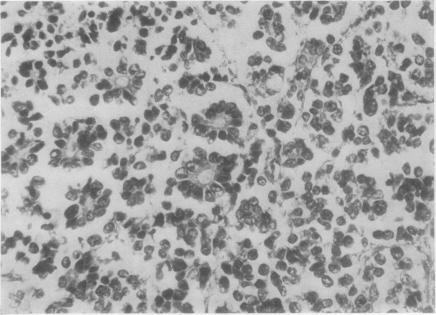

Carcinoid tumour of the uterine cervix.

A carcinoid tumour of the cervix in a 64-year-old woman is described. It is the first time that this rare tumour has been associated with carcinoma-in-situ.